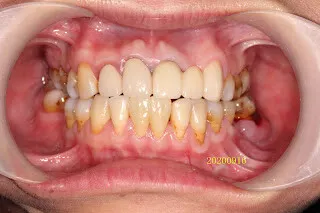

假牙材質2臨床案例...不同的假牙材質+牙齦萎縮